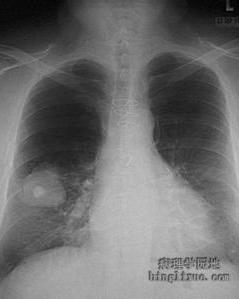

黄杆菌可引起肺炎,也可招致脑膜炎、败血症等感染,是一个新认识的菌种。[1]黄杆菌肺炎又称产黄菌肺炎,黄质菌肺炎。